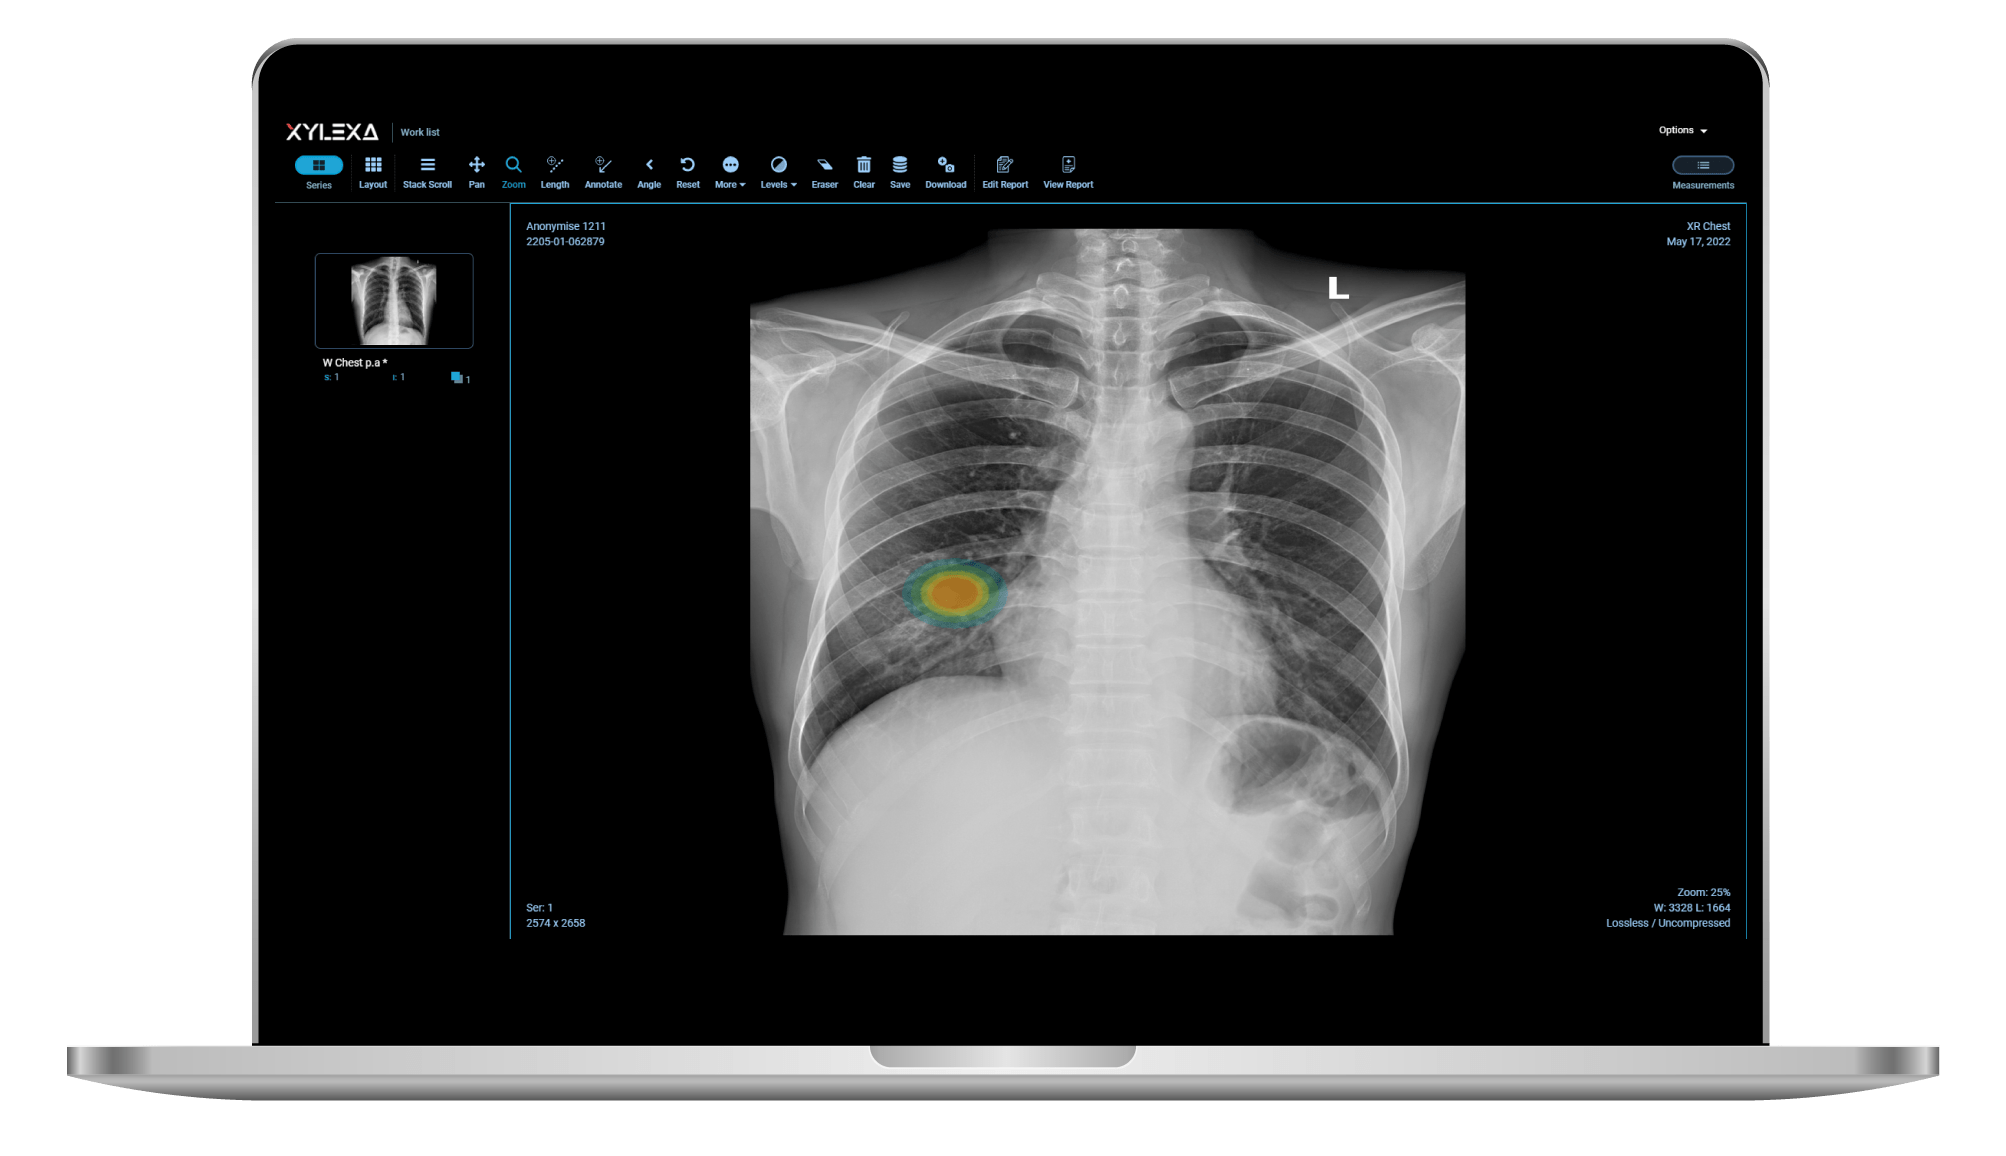

From xylexa.ai

XyCADCXR Xylexa Is Cxr Safe In Pregnancy In fact, the american college of obstetricians and. Exposure of an unborn baby to radiation may cause a slight increase in their risk from radiation. The higher the level of. For example, this is the. what are the effects on my baby? written by daphne metland. however, confusion about the safety of these modalities for pregnant and. Is Cxr Safe In Pregnancy.